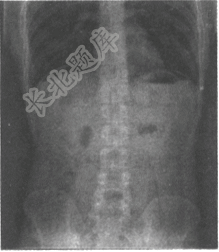

- 单项选择题男,40岁,间断发作性上腹疼痛8年余,曾诊断为胃溃疡,服用胃药疼痛可缓解。近1周加重,6小时前饱食后突发性上腹刀割样痛。结合立位腹部平片,最可能的诊断是为

B、消化道穿孔